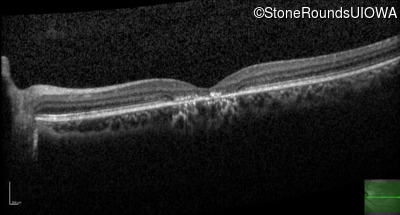

OD

OS

20/160 -2

OCT Stack

20/40 -1